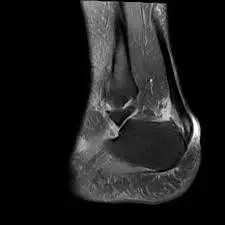

قطع جزئي في وتر القدم أو ما يُعرف بالتمزق الجزئي لوتر أكيلس هو حالة طبية تحدث عندما تتمزق بعض ألياف الوتر دون انفصال كامل للوتر، ويختلف قطع جزئي في وتر اكيلس عن القطع الكامل في أن الوتر يحتفظ ببعض اتصاله ووظيفته، مما يجعل خيارات العلاج أكثر تنوعًا ونسب الشفاء أفضل.

ويتميز الدكتور أحمد العطار بنهج علاجي شامل يجمع بين أحدث التقنيات الطبية والخبرة العملية الواسعة، ويمتلك مركزه أحدث أجهزة التشخيص بالموجات فوق الصوتية والرنين المغناطيسي لتقييم الإصابة بدقة عالية، مما يساعد في وضع خطة علاجية مخصصة لكل حالة.